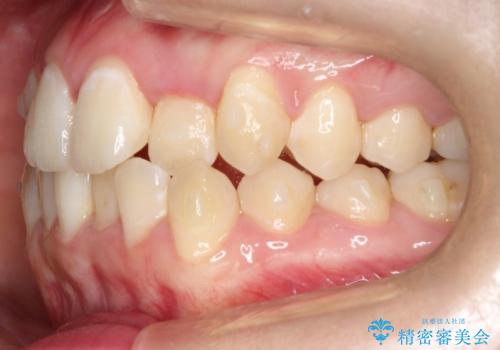

前歯が前後反対にかんでいる インビザラインによる矯正

- 前歯のがたつきを気にされて来院されました。

上顎の前から二番目の歯が内側に入り込んでおり、前後反対にかんでいる状態でした。

歯と歯の間にわずかに隙間を作り並べる計画としました。

しっかりとマウスピースを使用していただけたので、順調に治療を終えることができました。